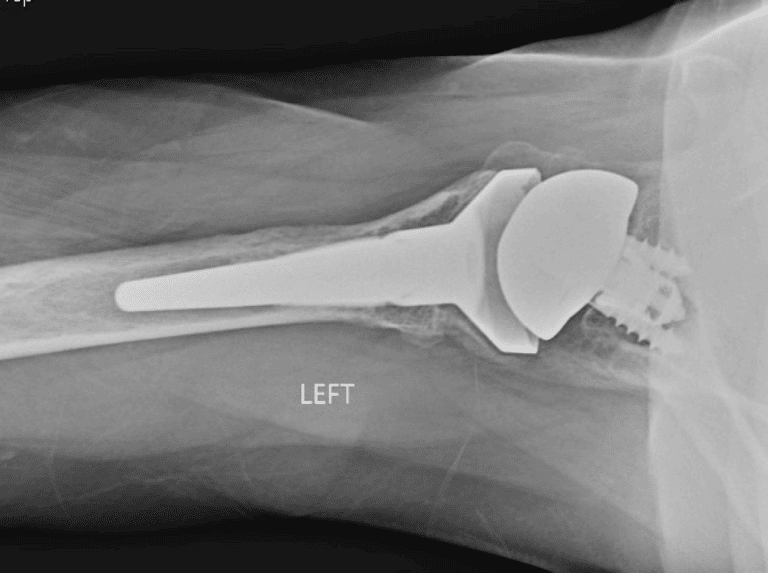

Lima, Hybrid

Selected